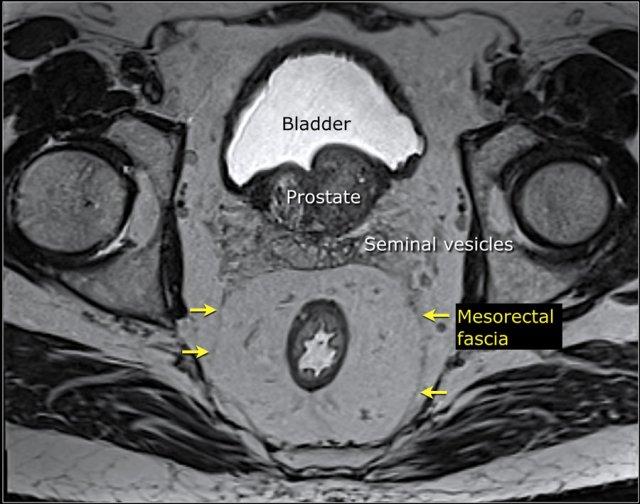

Hình minh họa cho thấy mạc treo trực tràng và mạc mạc treo trực tràng, đây là mặt phẳng phẫu tích cho phẫu thuật cắt toàn bộ mạc treo trực tràng (TME) và mối liên quan của trực tràng với cơ thắt hậu môn và sàn chậu.